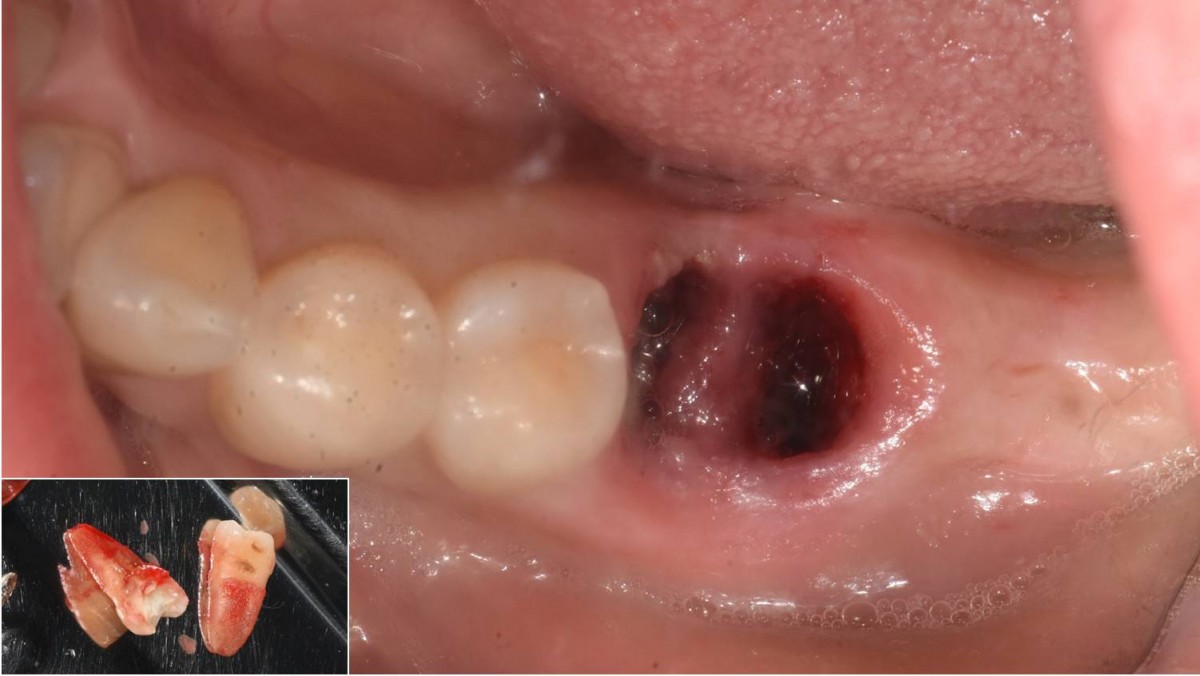

A 55-year-old female patient had

bilateral problems in both jaws.

It was decided to proceed with implant-supported restoration in the left molar part first.

She had been taking hypertension medication for a long time.